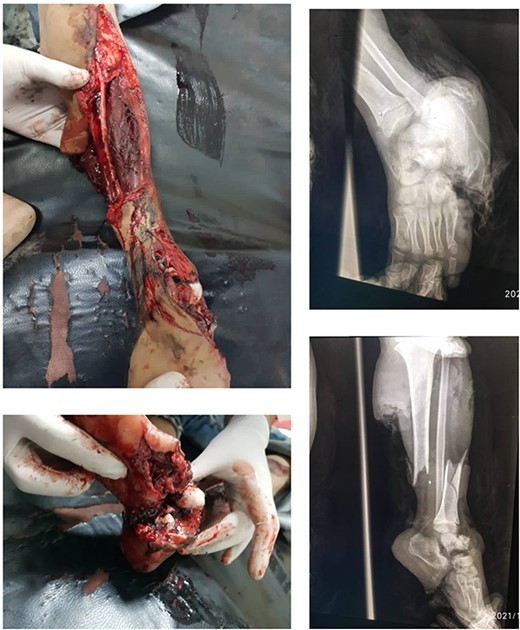

The decision to perform limb salvage surgery was made despite parental refusal and the consideration of the patient’s age. Initial debridement was performed in the supine position, with dislocations and fractures reduced and fixed using K-wires (Fig. 2). A temporary skewer was placed between the foot and the leg components to ensure stability. The patellar tendon, posterior muscles, and skin flap were meticulously sutured (Fig. 3). Postoperative follow-up showed satisfactory capillary refill, moderate sensation, and return of the anterior tibial artery pulse within three days. Progressive wound healing was observed over a month, allowing partial weight-bearing ambulation at 2 months (Fig. 4). Complete leg bone healing was achieved at 6 months, with removal of the flexible nail and restoration of the full range of motion and sensation (Fig. 5).

Shows the leg following the placement of the K-wire and prior to suturing the skin flap.